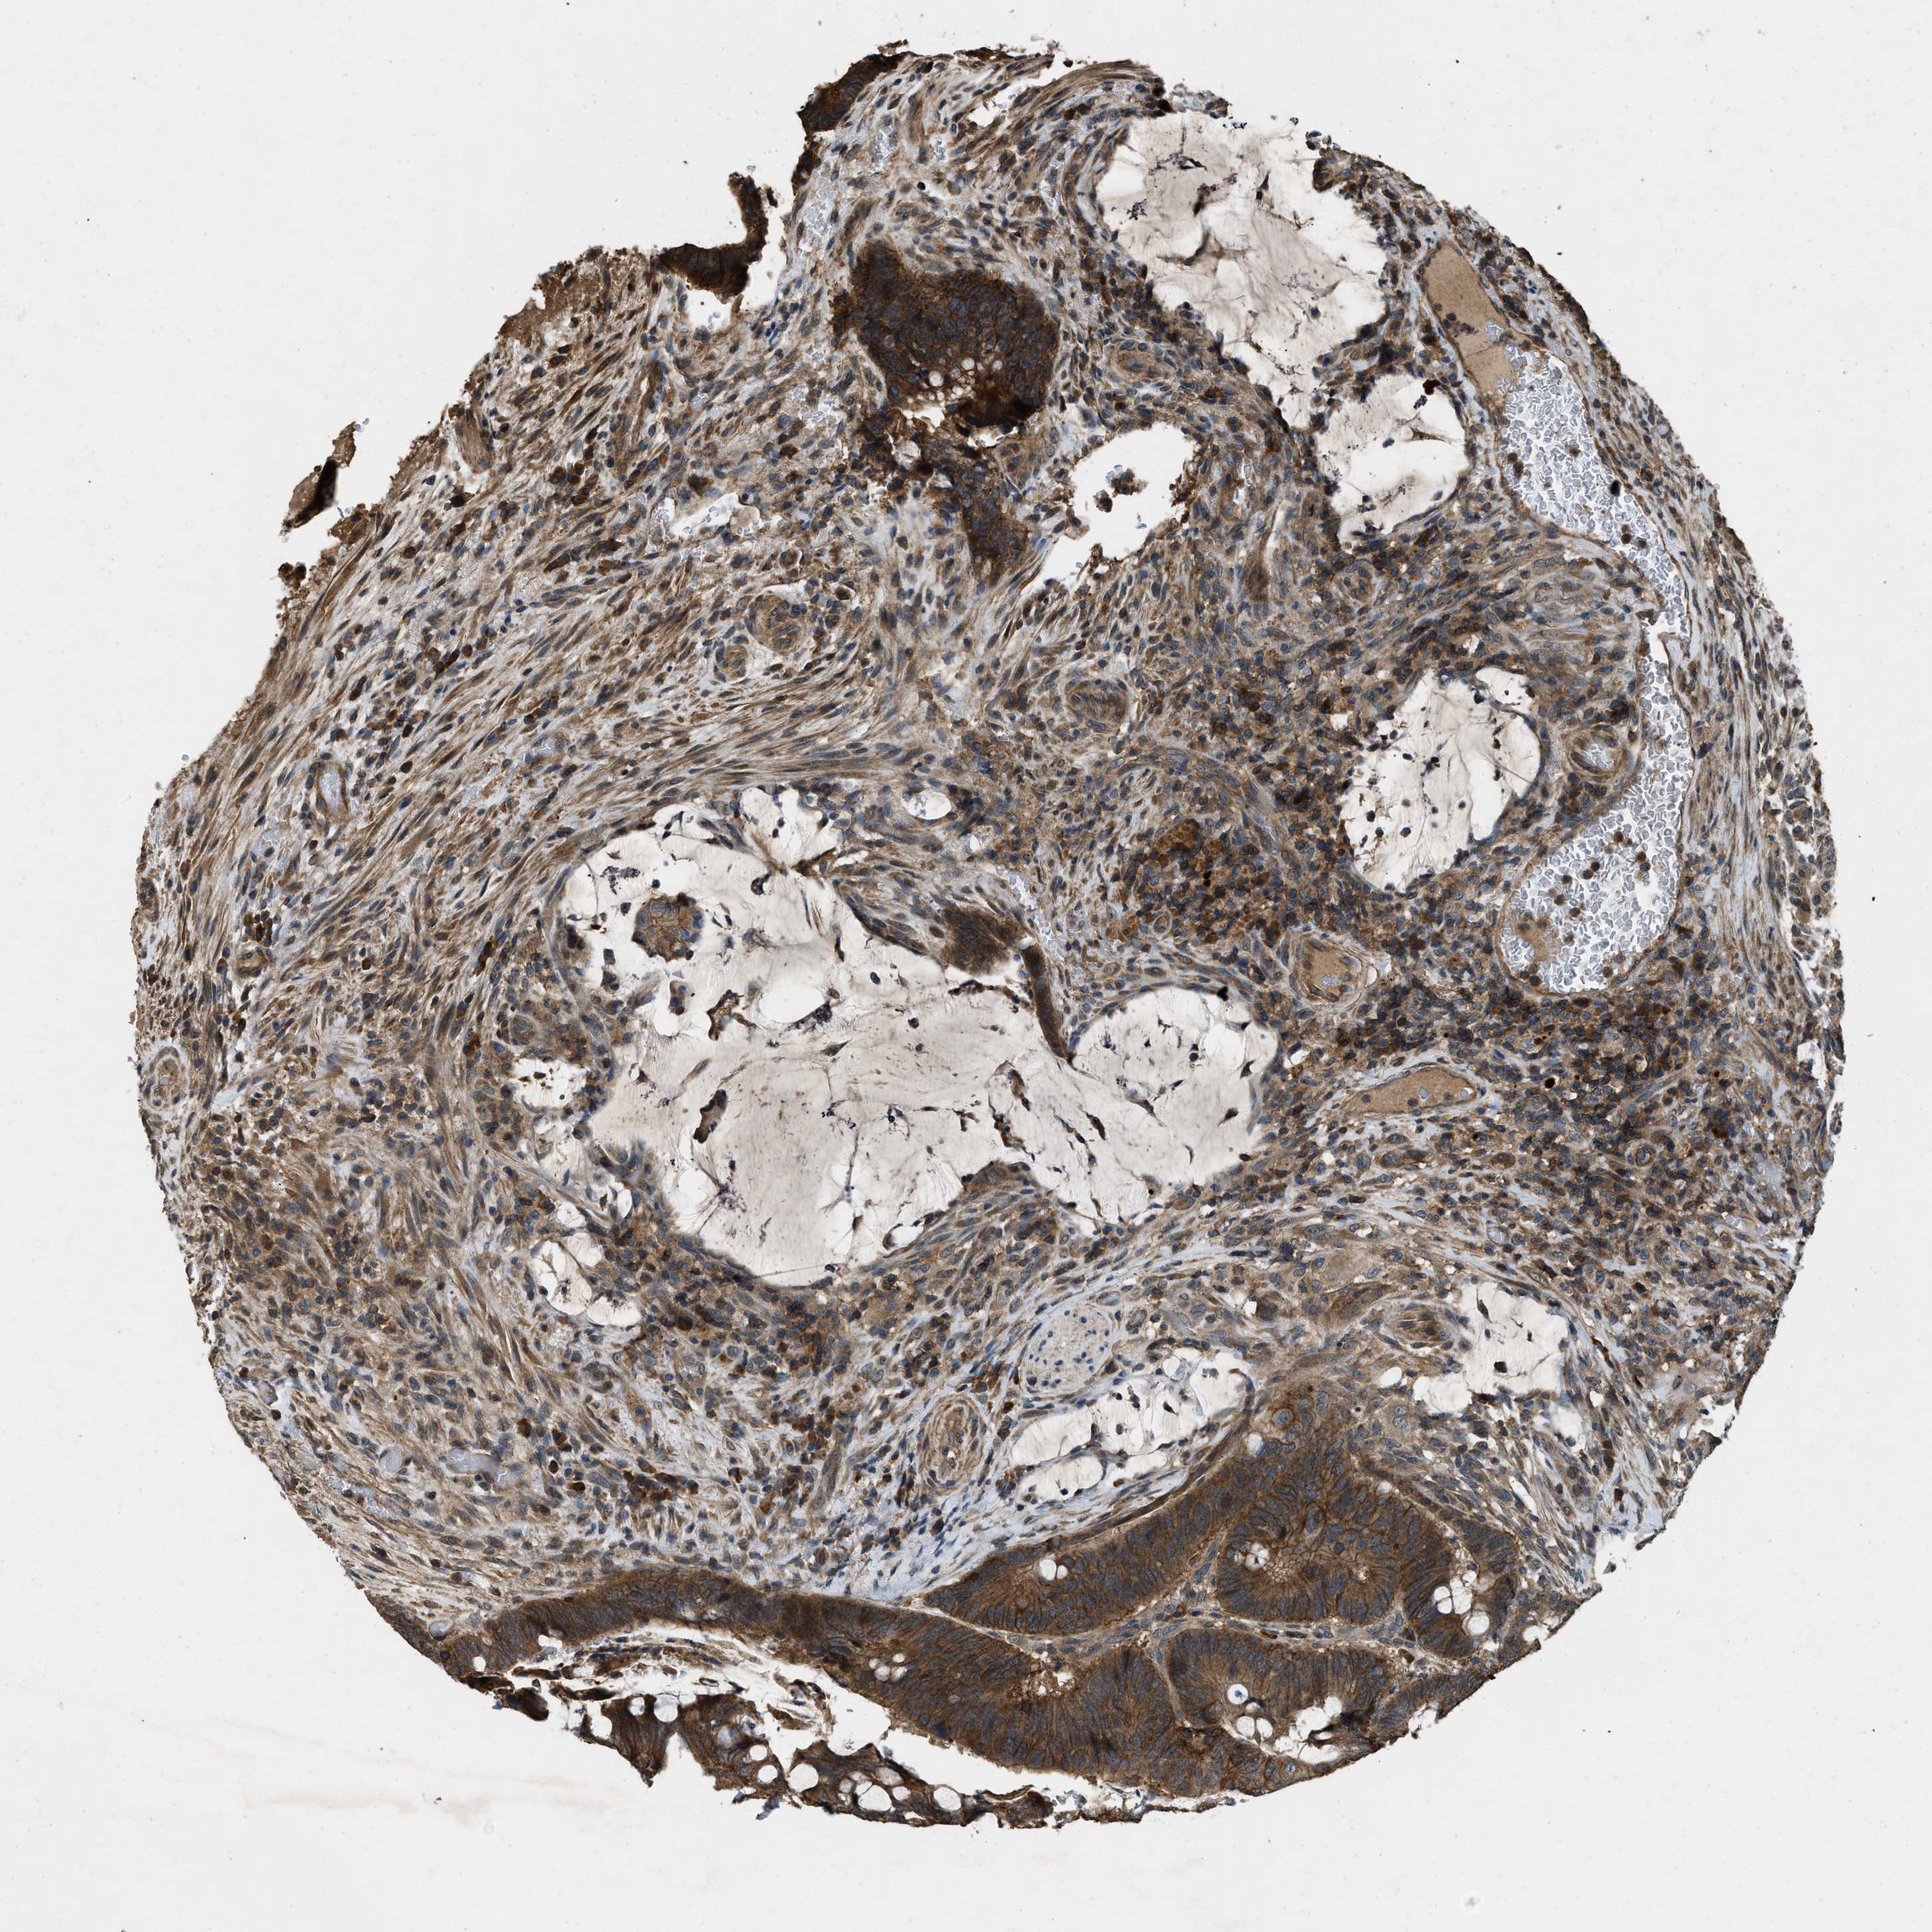

CANCER COLORECTAL CANCER Show tissue menu

Colorectal cancer

Human cancer

Colon adenocarcinoma